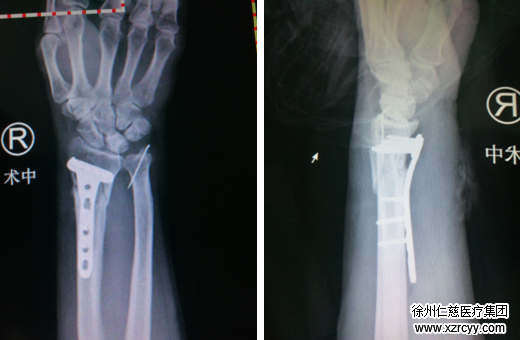

经检查:王阿姨尺骨桡骨闭合性骨折。手外三病区吴尧医生随即对王阿姨实施桡骨骨折切开复位内固定术。在右腕桡掌侧作一长约1.5cm纵行切口,将一块T型锁定板平行置于右桡骨掌侧,依次钻孔、功丝、测深,8枚金属锁定螺钉依次拧入,手术非常顺利。

一般情况下,放置T型锁定板需要开口3cm左右,而必威官方首页官网betway手外科利用显微技术,仅开口1.5cm上锁定板,创伤小,不影响腕关节活动,术后恢复快,5-7天即可出院回家,半个月内便可正常活动。王阿姨看到如此小的伤口,不禁赞叹:“谢谢你们,技术过硬,又替病人考虑,选择sararz真是太对了。”